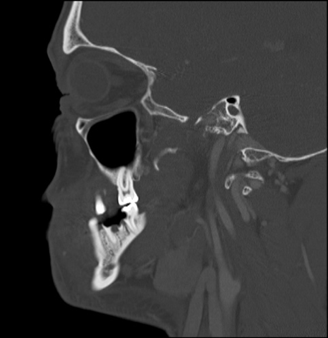

The results of contrast-enhanced maxillofacial computed tomography (CT) scans revealed an odontogenic facial soft-tissue abscess (Figures 1-3). There were partially missing first and second left mandibular molars with an adjacent rim-enhancing perimaxillary hypodensity consistent with a periapical abscess. Regional cellulitis and lymphadenopathy were present.

Figure 3. Sagittal bone window CT showing the fractured tooth responsible for the odontogenic abscess.